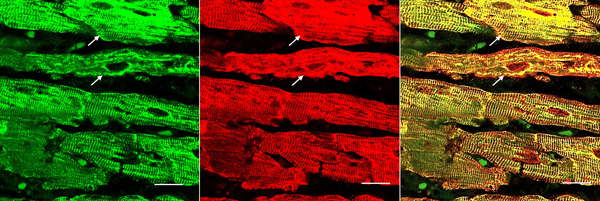

Double-label laser scanning confocal immunofluorescence: Figure 6 shows the colocalization of desmin and αB-crystallin in Z-discs and intercalated discs. In FA, intercalated discs are wider at approximately 50 µm than normal (approximately 23 µm) and have undergone chaotic disorganization (fig. 6d). A more advanced fiber destruction is illustrated in figure 7. Two adjacent fibers display accumulation of desmin and αB-crystallin, obliterating the contractile apparatus of the cardiomyocytes. A search for amyloid by polarizing light for apple-green birefringence and Congo Red fluorescence did not reveal amyloid deposits. Figure 8 shows double-label immunofluorescence of desmin and ATP5B. All fibers in FA contain clusters of mitochondria, visualized by green fluorescence of ATP5B, and one cluster is surrounded by a rim of desmin. In normal cardiomyocytes, mitochondria occur in rows of delicate granules between heart fibrils (fig. 8, top row).

Figure 7. Desmin and αB-crystallin overload in FA cardiomyopathy (same patient as in fig. 6). Desmin is shown as Alexa Fluor 488 green, αB-crystallin as Cy3 red, The merged image on the right shows extensive colocalization of these protein and destructive aggregation in two fibers (arrows). Bars, 10 μm.

Figure 8. Double-label laser scanning confocal immunofluorescence microscopy of desmin and ATP5B. Top row, normal control; bottom row, FA (same patient as in fig. 5). Desmin is shown as Cy3 red, ATP5B as Alexa Fluor 488 green. In the normal control, mitochondria appear as rows of punctate green organelles aligned along fibrils. In FA, green mitochondria appear in clusters (arrows). The upper cluster is surrounded by a desmin deposit. Bars, 20 µm.